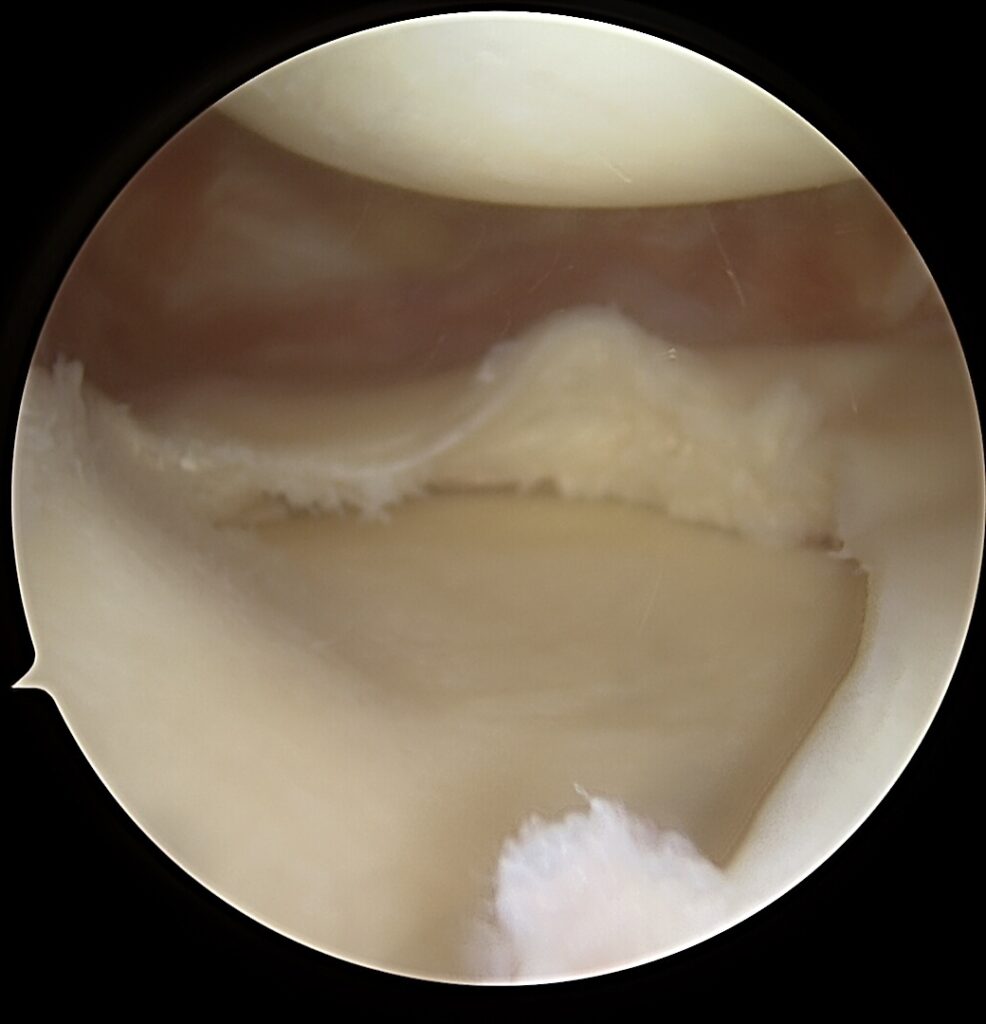

🎯 Kodėl svarbi vienmomentė kompleksinė rekonstrukcija?

- Mažesnė pakartotinių operacijų rizika

- Geresnis stabilumas ir funkcija

- Greitesnis ir aiškesnis reabilitacijos planas

- Didesnė tikimybė grįžti į aktyvų gyvenimą